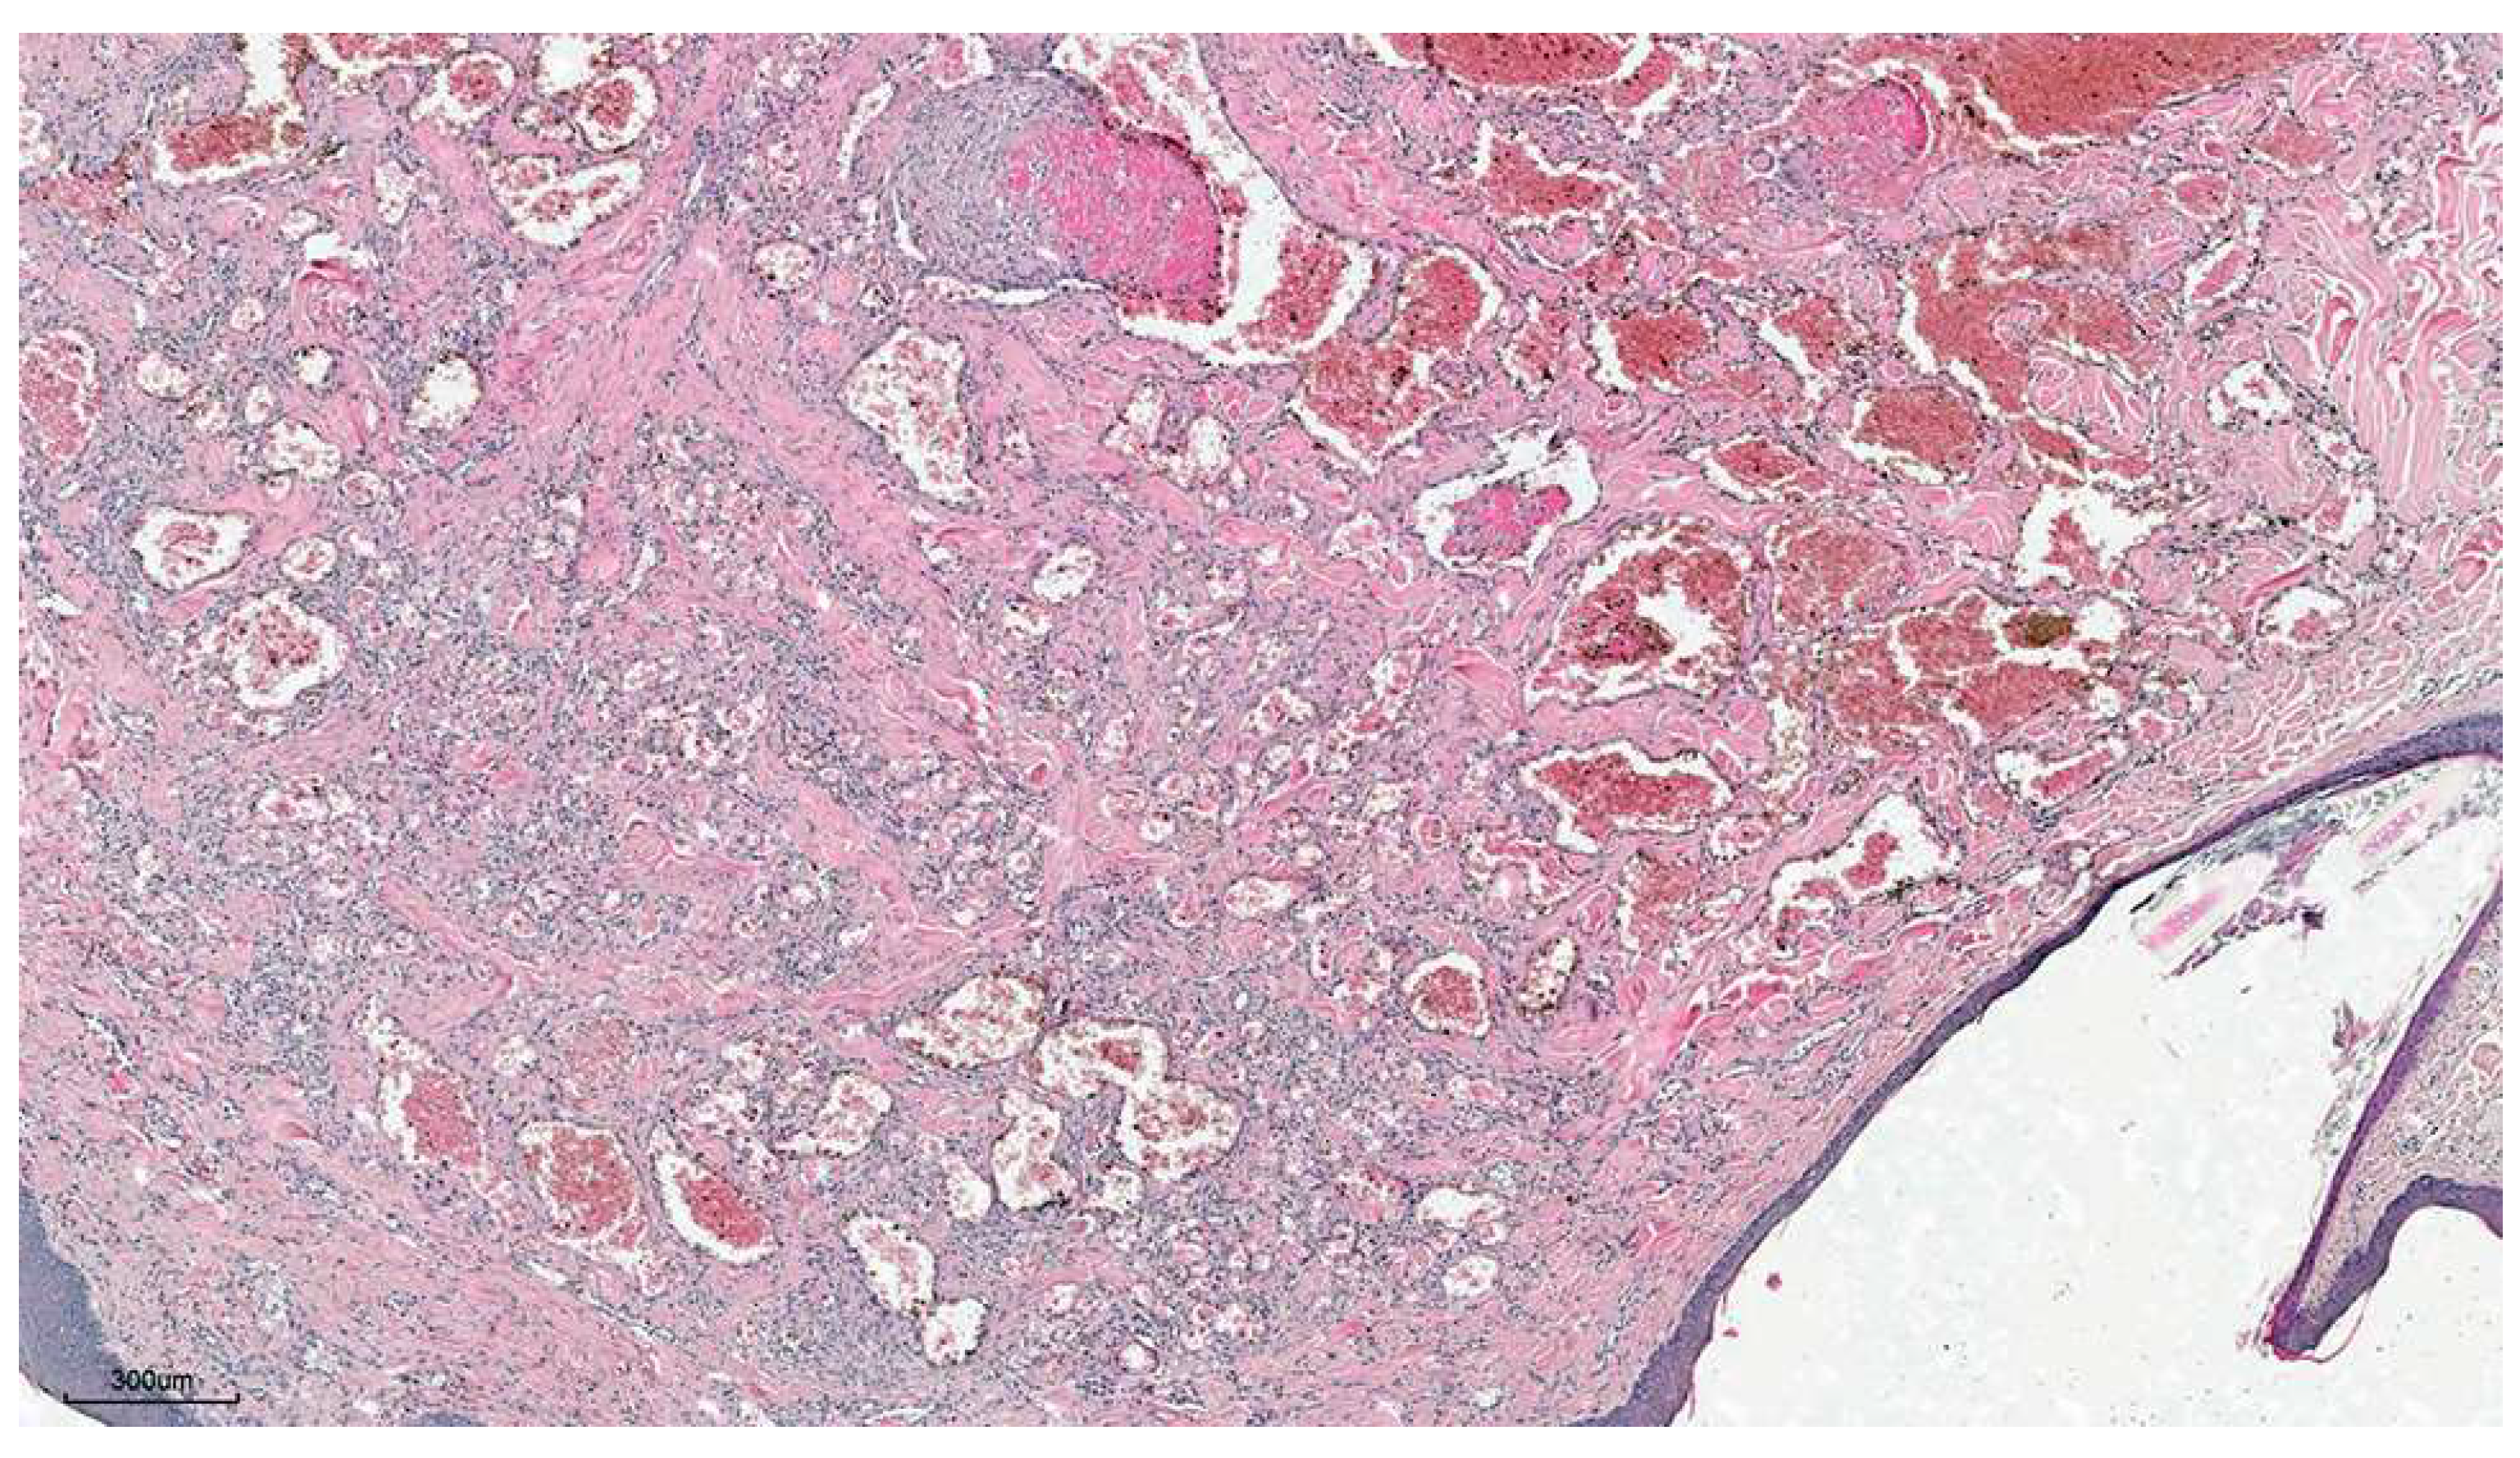

3.1.2. Histopathology

3.1.3. Immunohistochemistry

3.2.2. Histopathology

3.2.3. Immunohistochemistry